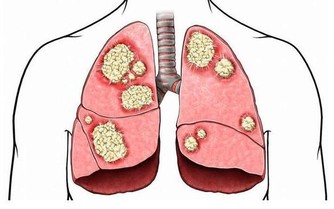

體內濕氣重的人,是健康的隱憂,一旦與外來的濕氣裡外相合,就更加糾纏不清了,這也是濕氣重的人一遇到陰雨天或梅雨季節,濕濁阻遏氣機與清陽,時常會覺得頭昏沉、提不起勁、很想睡覺、四肢沉重無力、大便變的軟黏的排不乾淨、胃口不好、嘴巴淡淡的沒什麼味覺,甚至皮膚濕疹發作或搔癢加重…從中醫的觀點來看,水腫病與肺、脾、腎三臟關係最大,身體的水分代謝是透過肺的通調水道、脾的運化轉輸和腎的溫化蒸動等生理功能協調下完成,而中醫在治療水腫原則,有「腰以上腫發汗腰以下腫利小便」一說,再搭配不同病因病機去調理。

肺能通調水道,肺失宣降則水津不布